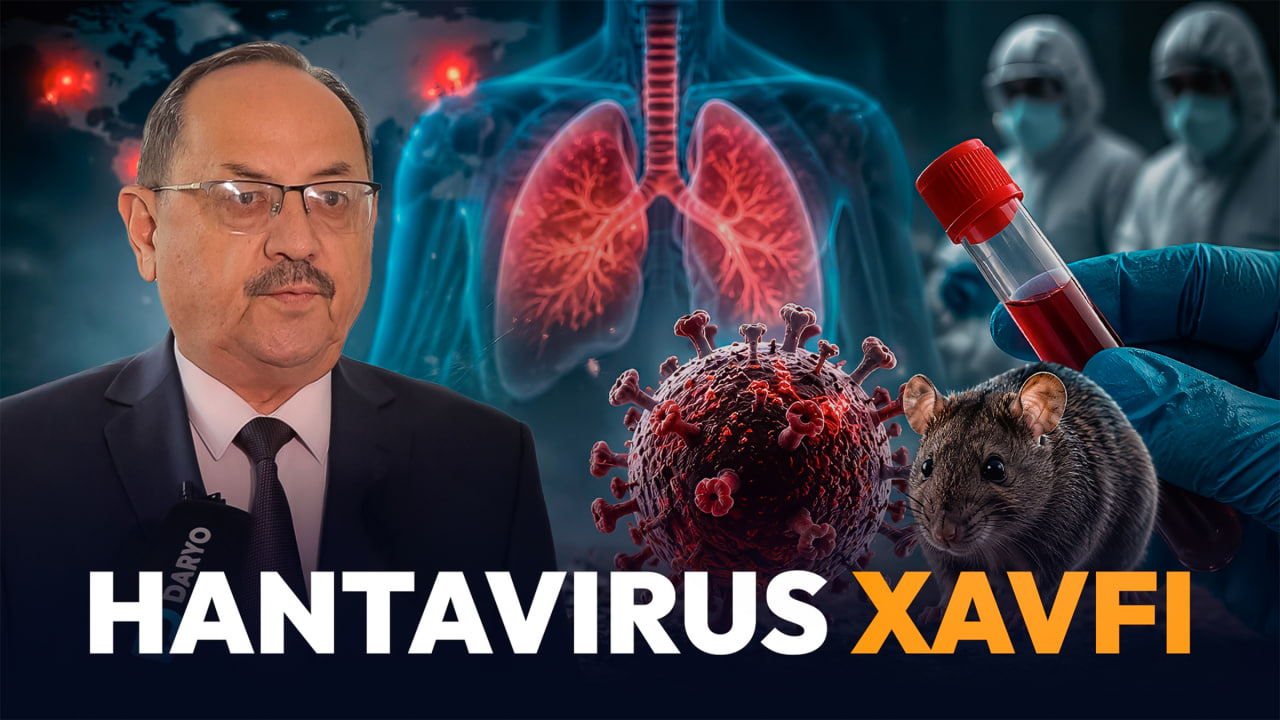

«Ҳантавирусга қарши вакцина йўқ» — Нурмат Отабеков